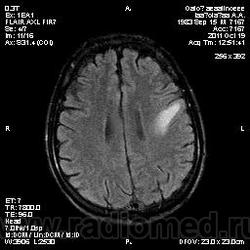

Молодой человек, жалуется только на головные боли и слабость в правой руке и ноге (около месяца).

Пациент полуасоциальный, нельзя исключить анамнез наркоманский....

ППН (включая ячейки пирамидок и сосцевидные отростки) тотально заполнены жидкостным компонентом...

Колеги, спасибо за высказывания. В данном случае про наркоманский анамнез указано не спроста... Есть мнение, что в этом лежит точка отсчета.... По поводу абсцесса и гематомы - не согласен; по поводу первого - нет соответствющей клиники, по поводу второго - не характерна локализация и сигнальные характеристики. Не буду томить общественность касательно собственного мнения. Есть две гипотезы, о которых думается в данном случае: прогрессирующая лейкоэнцефалопатия и новообразование... Но без контраста их не разрешить...

пожалуй "первое", но в отношении "второго"смущает "круглит" на вершине "воспалительной демиелинизации", который она (демиелинизация) так странно обходит...

Имеются  в виду последние 2 картинки?Мне тоже так показалось.А почему контрастирования не будет?Чем контрастируете?